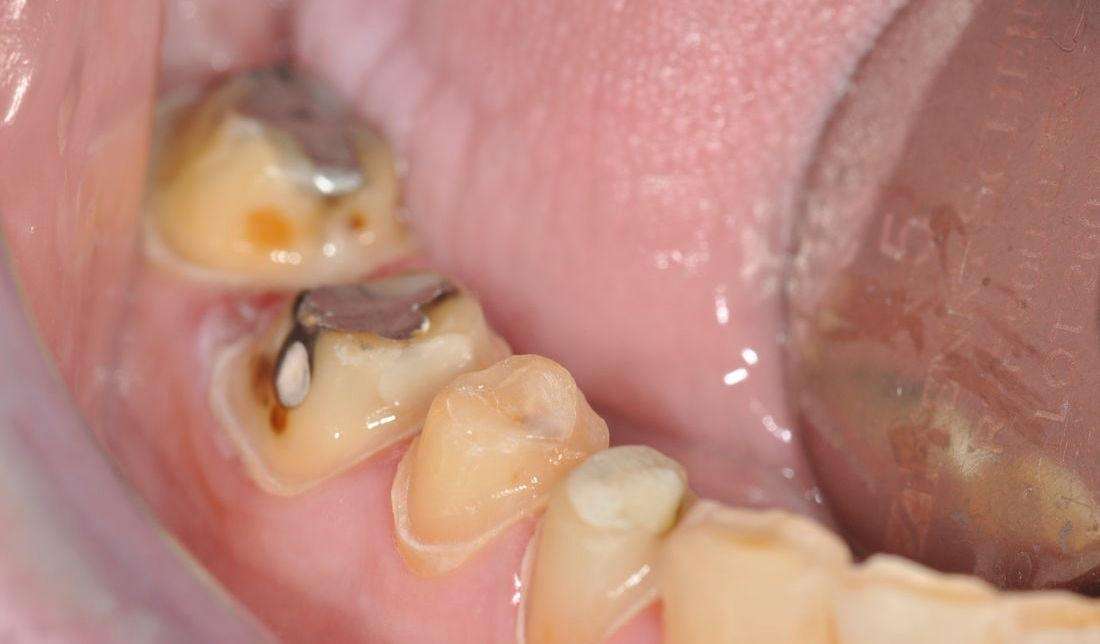

Crown

Click image to see a larger picture

Before